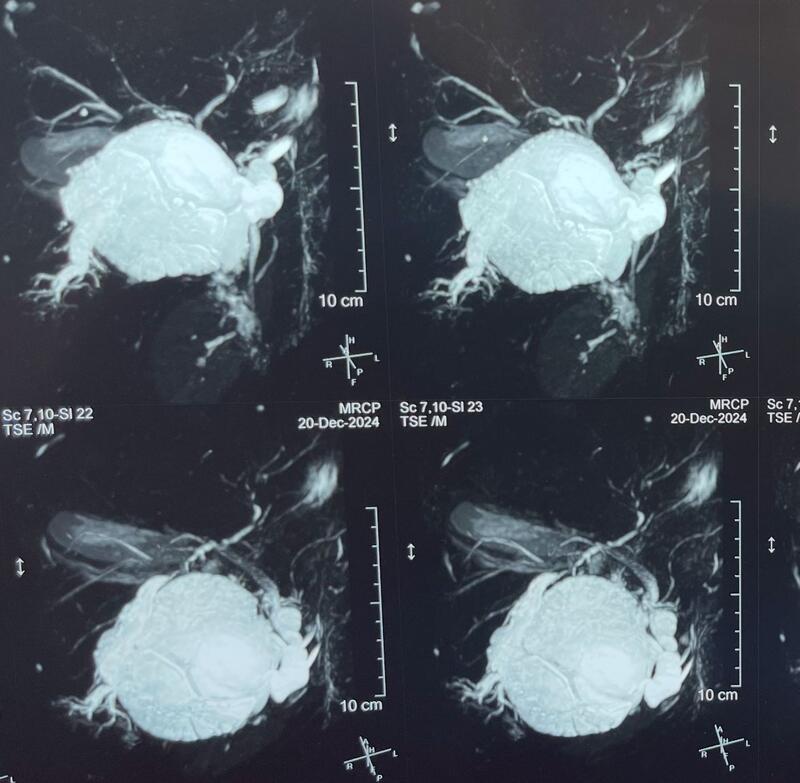

Blood investigations showed obstructive jaundice. CT Abdomen and pelvis with MRCP confirmed a large hydatid cyst in the right lobe of the liver measuring 12x14 cm, compressing the right biliary ducts (posterior ducts), with no obvious biliary communication. Associated cholecystitis with sludge in the gallbladder was also noted.